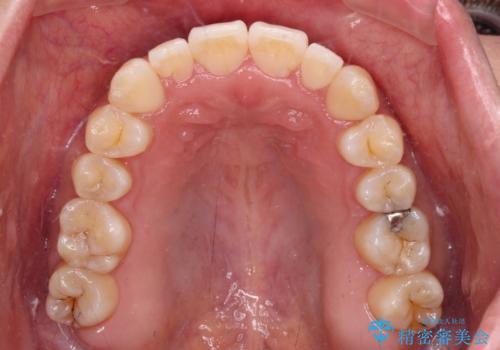

すきっ歯とオープンバイトをインビザラインで改善

- 前歯の上下スペースと前歯の隙間を気にして来院された患者様です。

インビザラインにより上下の前歯の隙間を閉じていくこととしました。

上下の隙間に舌が入り込むことが、すきっ歯やオープンバイトの原因であったため、舌の筋肉のトレーニングも並行して行い、後戻りの抑制を図りました。